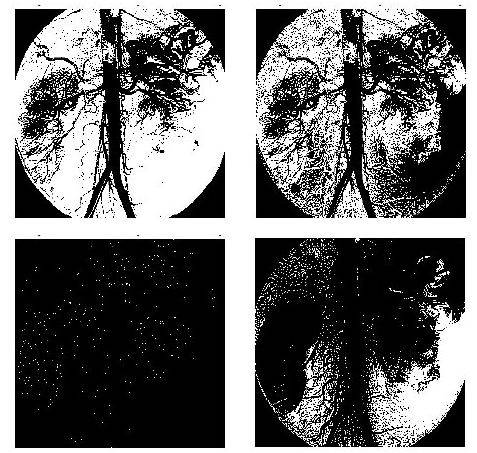

Es oportuno preguntar qué ocurre si solo se tiene el caso clásico de blanco y negro o una tonalidad de gris y negro. La Figura 4 se construye al tomar un rango de pertenencia dada por una tonalidad clara (inferior izquierda), oscura (inferior derecha) y media (superior derecha) del color gris (en formato RGB son respectivam&e, (211,211,211), (120,120,120) y (173,173,173)) y se aplica el operador apertura a cada una de las imágenes generadas al aplicar el rango de pertenencia a la imagen original. Al unir estos intervalos de pertenencia en la escala (superior izquierda) se obtiene que la superposición de una con la otra da un mejor panorama de la imagen a analizar. Es así como se hace necesario una lógica de más de dos valores. Como se mostró en el sección anterior, si se aplica un número par de veces el operador apertura siempre que la relación estructural cumpla las condiciones del Teorema 4 es lo mismo que aplicarlo dos veces (debido a la idempotencia del operador), lo cual deviene en una reducción en las iteraciones que debe realizar el ordenador para arrojar la resonancia aplicando un filtro que genere como resultado tan solo las cavidades sanguíneas del paci&e. En este caso se toma una relación estructural clásica, donde el elem&o estructural es un cuadrado de 2.2 píxeles. En la Figura 5, se exhibe la imagen original y el operador apertura aplicado una y diez veces.

Ahora, la Figura 6 se obtiene al filtrar con una relación (elem&o estructural forma de L d&ro de un cuadro de 4.4 píxeles) que no satisface las condiciones del Teorema 4, para así resaltar la pérdida de información en el resultado que incide negativam&e en el juicio del facultativo; al evaluar que elem&os son taponami&os y cuáles son naturales del sistema circulatorio del paci&e; el ruido que aparece está resaltado en rojo.